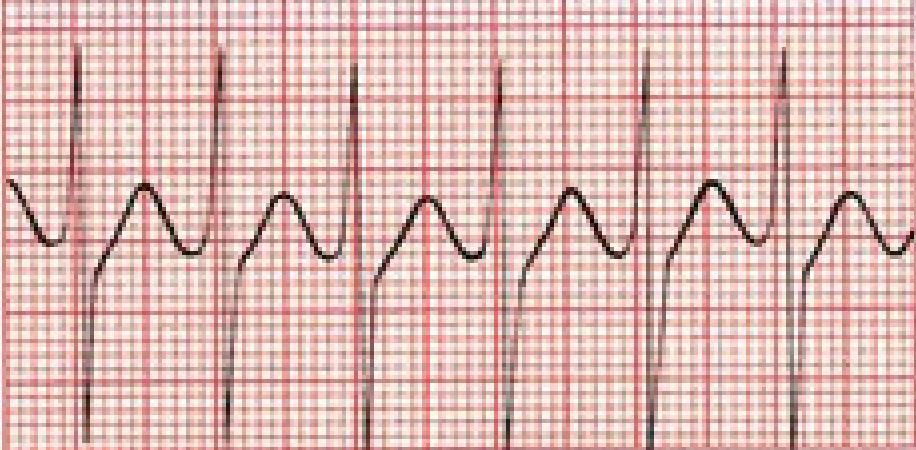

Is this EKG normal?

A typical rhythm strip. It can be as short or as long as you need to decipher the rhythm. This particular strip represents a continuous recording of lead II in a patient with normal sinus rhythm, the normal rhythm of the heart.